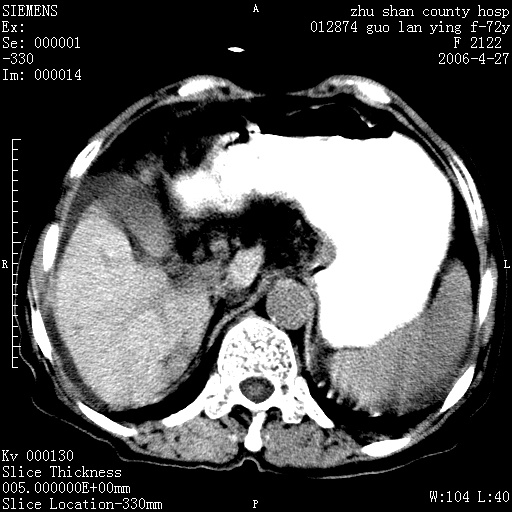

病人 女性 72岁 b超要求ct检查!

平扫所见:胆囊区两点壮高密度影,灶周有伪影{请问楼主患者有手术病史?}。肝实质内未见明显异常{建议强化或mri}.腹腔有少量积液,脾明显增大.右肾形态似不规则?

腹腔内示积液征,脾脏略增大,肝脏由于运动伪影较多,影响观察,内未见明显高密度区,胆囊内示两处高密度结石。胃窦部壁轻度增厚。另外,肝脏的前缘似有游历气体。不知病人的临床如何?有必要做胃的检查,还有,看看骨窗是否有腹腔游离气体还是肠管影响的。

如果b超对肝脏有怀疑,肝脏的增强扫描还是尽量去做。

肝脏缩小,脾脏增大,肝脾外缘及胆囊窝液性密度影,肝脾ct值正常,胆囊区见两个类圆形高密度影,下腔静脉前方类圆形软组织密度影为肝脏岛叶,胃幽门区见软组织密度影,十二指肠钡剂充盈不好.

1:腹水2:胆囊结石3肝硬化?(不确定,请结合临床)4幽门区占位?(建议胃肠透视)

肝硬化,脾大,少量腹水

肝硬化、脾肿大,腹水,胆囊区高密度影(结石或异物),是否有外伤史

肝硬化、腹水、脾大,胆囊结石可以肯定。只是肝右叶两个低密度有必要增强确定一下;排除小肝癌。

谢谢牟教授在百忙之中还认真的点评我的帖子!也谢谢大家的鼎力相助,此病人是我们医院护理部主任的母亲!病人以前无特别不舒适!昨天b超后发现有问题!做ct的目的在于排除肝内占位性病变,此病人以前无手术外伤史.